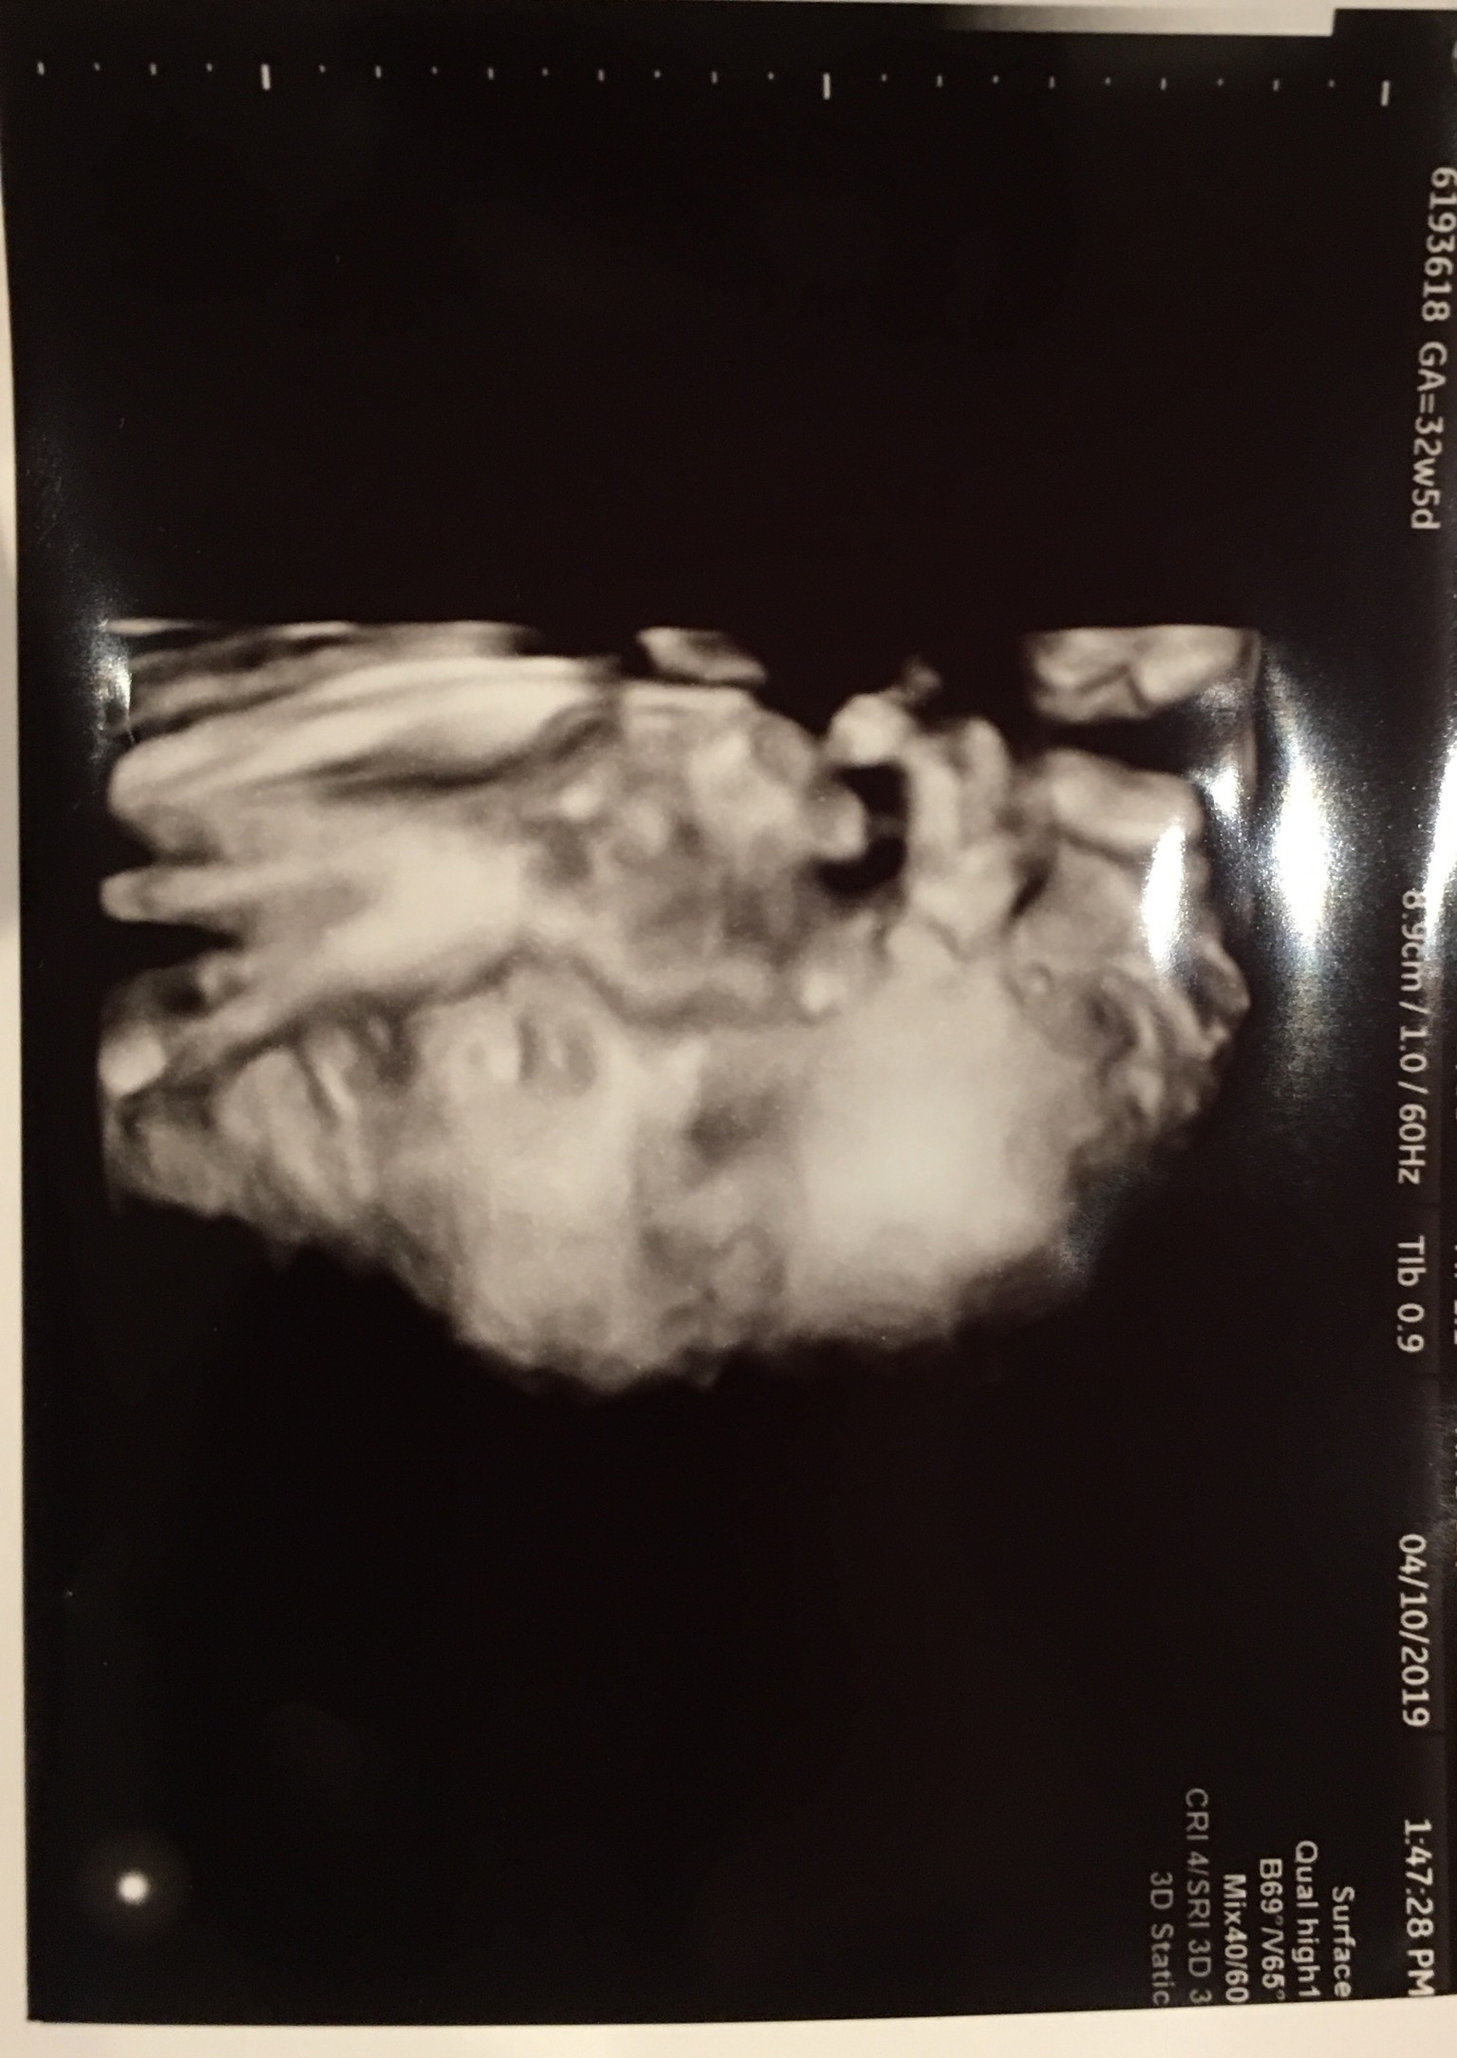

heres a hdbd for 32+0 today: